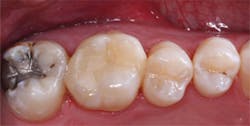

Use of resin-modified glass ionomer as a liner or base

The following technique is for use of RMGI as a liner or base for direct resin-based composite restorations using a self-etch bonding agent. Use of total-etch or selective-etch would be slightly different. Any of the three techniques works well if accomplished properly.

- Place resin-modified glass ionomer on the deepest areas of the tooth preparation, not on the margins. The material should be about 0.5 mm thick or slightly thicker. Cure it.